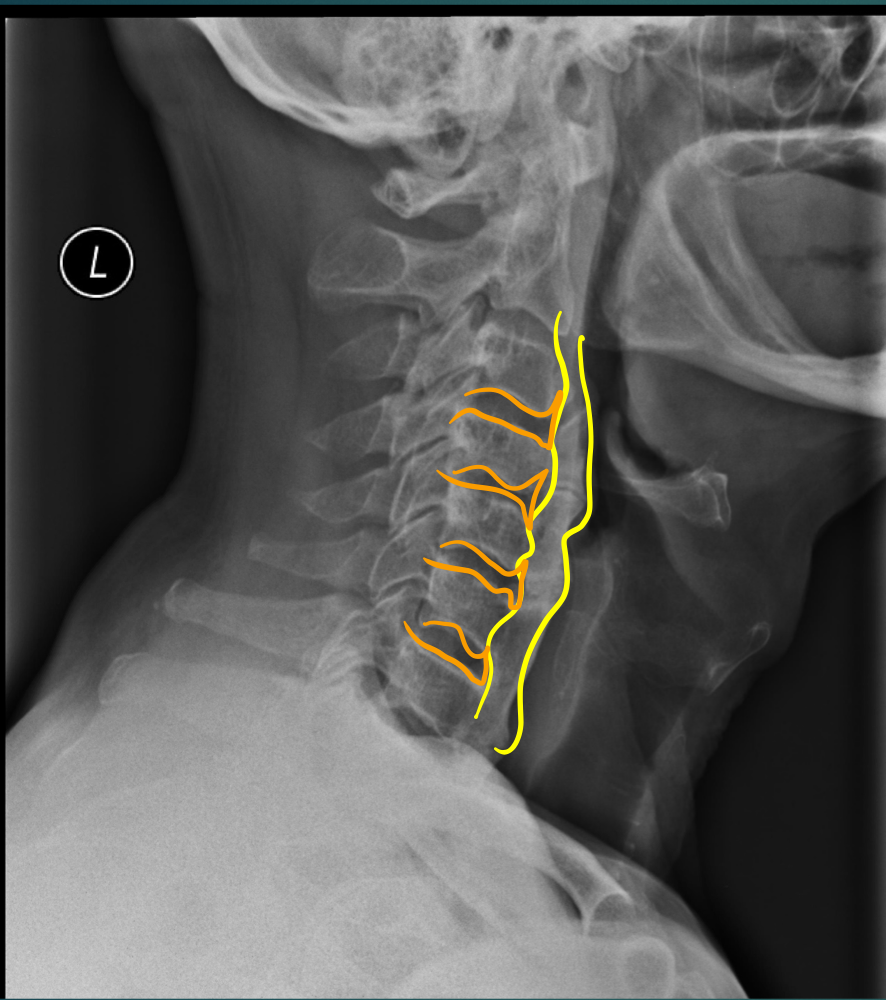

52 YO M. Complains of difficulty with eating.

• Hyperostosis of ALL

• NORMAL disc height

• T or L shape (orange)

• Look for OPLL 85% of the time - look for this because of central canal stenosis

Think: DISH